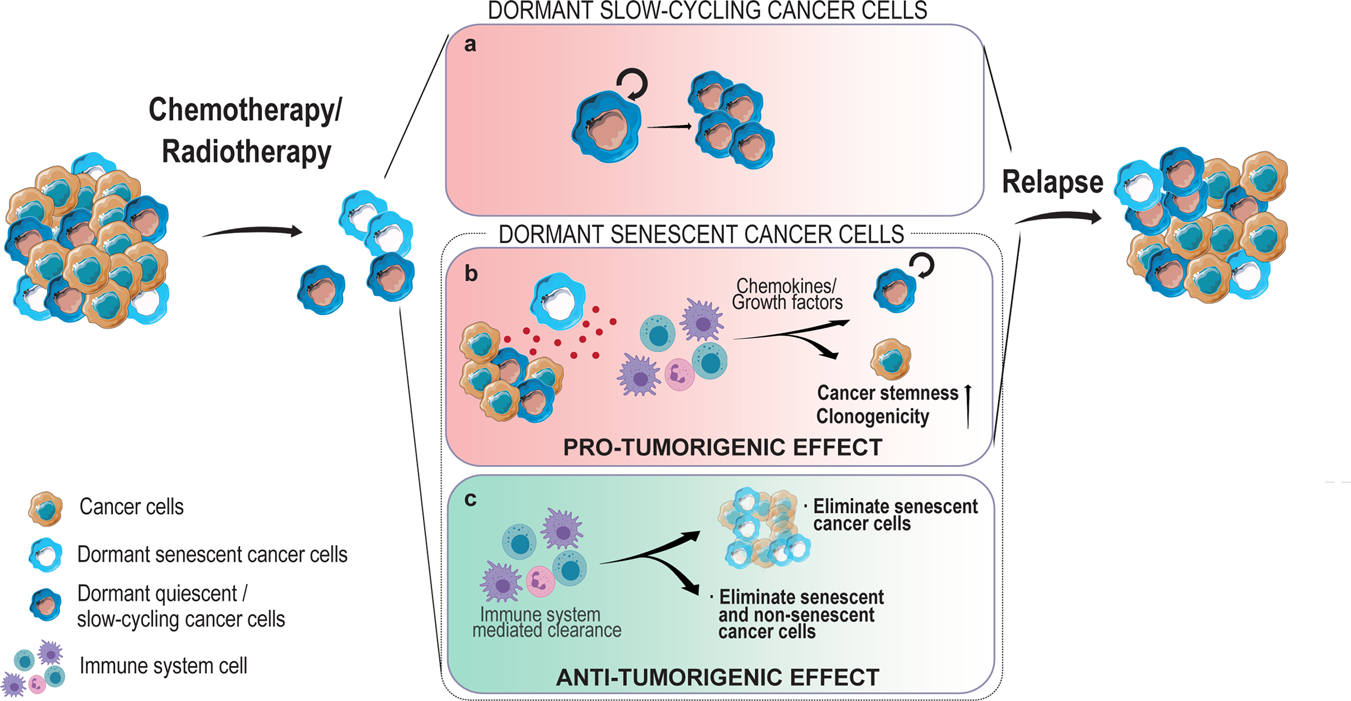

When dormancy fuels tumour relapse